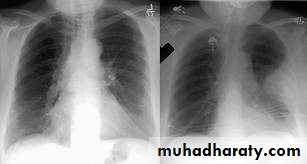

CXR may show opacities (of any size or shape); more specifically it may show horizontal linear opacities or wedge shaped pleural based opacities. Pleural effusion or raised hemidiaphragm may be noticed.

CXR is commonly normal (or show subtle oligaemia).

The ECG may show tachycardia only, the CXR is commonly normal. Both investigations are more useful in excluding other diagnosis like MI (ECG), pneumonia and pneumothorax (CXR)